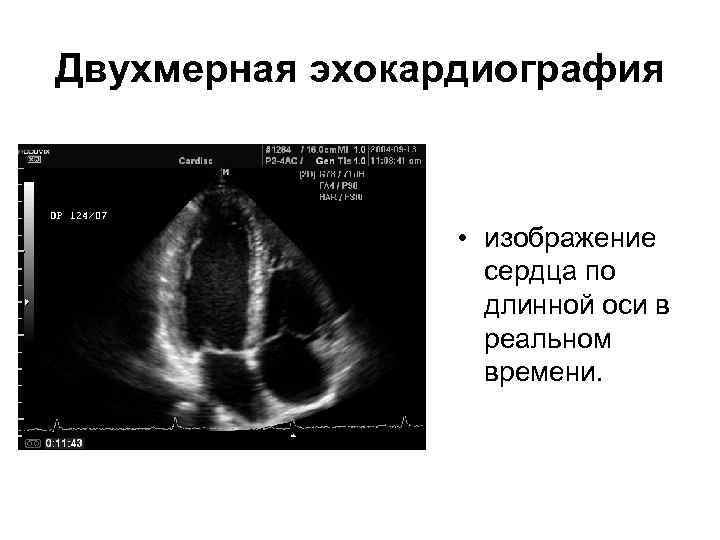

Двухмерная эхокардиография • изображение сердца по длинной оси в реальном времени.

Двухмерная эхокардиография • изображение сердца по длинной оси в реальном времени.